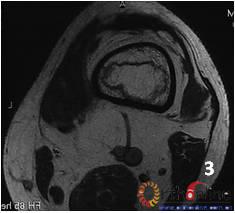

2. 发生在骨端(股骨头、肱骨头等)的坏死称为骨坏死(osteonecrosis,ON)。ON有两种类型:单纯骨髓坏死,软骨下骨(皮质骨)部分保留;骨髓坏死连同皮质坏死。

图 3 男,53岁,激素相关股骨头坏死,MRI(2003年)示右侧L1型坏死(皮质存留,骨髓坏死),左侧L3型坏死(皮质及骨髓均坏死),三年后(2006年)及6年后(2009年),CT扫描示右侧股骨头维持圆形,骨皮质完整,但中央坏死灶未修复;左侧股骨头塌陷

Fig 3 Male, 53 year-old, steroid-associated ONFH, MRI(2003) showed type L1 necrosis(cortical bone was preserved, necrosis in bone marrow) in right side; type L3 necrosis(both cortical bone marrow) in left side. CT scan showed the right femoral head keep round, and collapse occurred in left femoral head three (2006) and six year (2009) later.

3. 两种类型的ON有不同的结局,前者预后较好,而后者预后差。(图3)